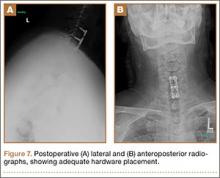

Intraoperative lateral fluoroscopy was obtained to confirm the C5-C6 and C6-C7 level prior to discectomy. The musculature of the patient’s neck and shoulder made visualization of the C6-C7 disc space difficult on the lateral radiograph (Figure 5). One attempt was required to obtain the 30º–30º oblique view, which was used to ensure correct placement of the screws and plate (Figure 6).

Postoperatively, the patient’s pain had improved, and radiographs confirmed adequate hardware placement. He was discharged 1 day after surgery (Figure 7). Imaging at the patient’s 6-week follow-up confirmed adequate fusion from C5-C7, stable disc spaces, and anatomically aligned facet joints. His Neck Disability Index was 34/50 preoperatively and 32/50 at 2-week follow-up.